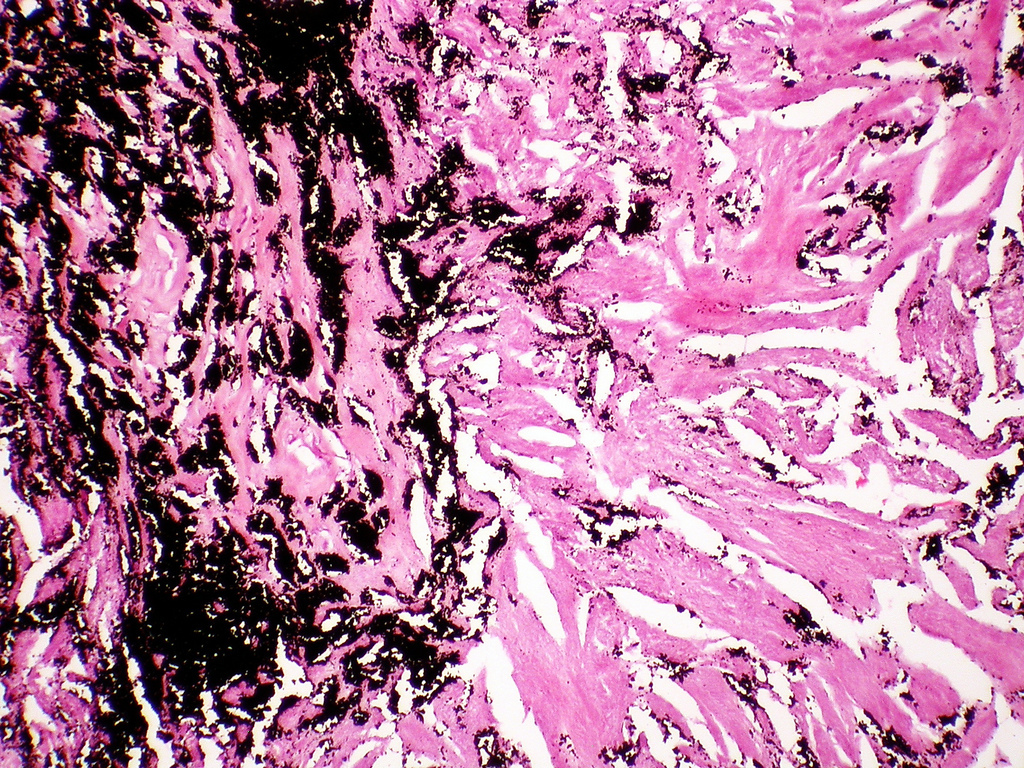

Coal- workers pneumonia (CWP)

“black lung disease”

is an occupational disease (type of pneumoconiosis) caused by exposure to coal dust free of silica (washed coal).

the spectrum of lung fidings vary from

1) atmpytomic anthracosis

2) simple CWP w/ little or no pulmonary dysfunction

3) complicated CWP w/ fibrosis!

in a nutshell>> prolonged coal dust exposure> alveolar or intersitial macrophages loaded with carbon> Inflammation and FIBROSIS

blackened scars in UPPER LOBE, since its next to the respiratory bronchi (site of initial dust acummalation)

may lead to FIBROSIS> Emphysema & chronic bronchitis

anthracosis: “the asymptomatic, milder type of pneumoconiosis as caused by the accumulation of carbon in the lungs due to repeated exposure to air pollution or inhalation of smoke or coal dust particles”